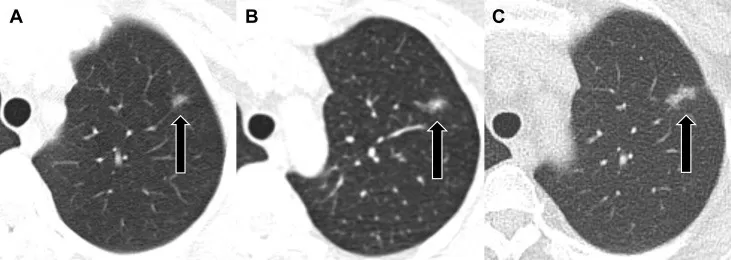

Hình 1: Hình ảnh chụp CT phổi liều thấp tầm soát và theo dõi nốt ở phổi ở một bệnh nhân nữ 36 tuổi khoẻ mạnh.

https://www.jto.org/article/S1556-0864%2819%2930368-5/fulltext